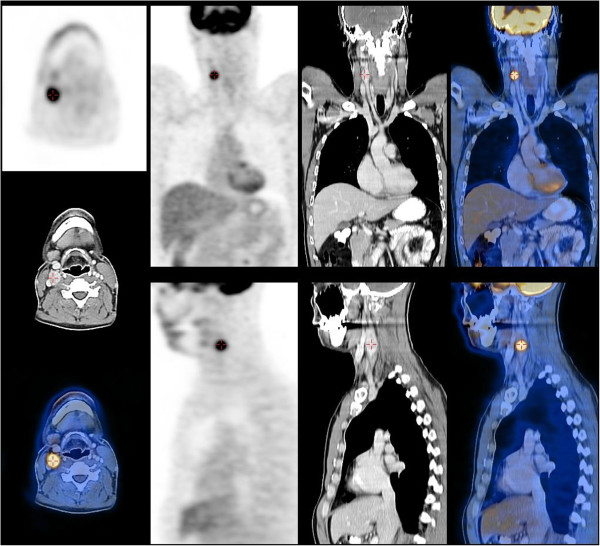

A 36-year-old man presented with a newly discovered mass on the right side of his neck. A year before, he had been treated for testicular cancer classified as a stage I combined germ cell tumour (pT2N0M0). After orchidectomy, the patient was engaged in active follow-up.A few days prior to his regular follow-up visit, he noticed a neck mass. He had no additional complains. Abdominal and testicular US scans, a chest X-ray and blood tests were normal at the time. On clinical examination, a palpable, 2 × 1.5 cm tumour on the right side of his neck was detected. The patient was sent for a FNAB. The smear was described as poorly cellular, composed predominantly of naked nuclei in a haemorrhagic background. The majority of the cells were small, with round nuclei, mixed with some larger cells, which gave the sample an appearance of obvious anisonucleosis. Cytoplasm was seen only in a few cells and gave cells a plasmacytoid appearance. The sample was diagnosed as a lymph node metastasis of a teratomatous component of the germinal tumour or of another primary tumour. Figure 1 represents a FNAB smear of the patient’s tumour.An ear, nose and throat specialist did not discover any suspicious lesions. A neck US scan revealed an enlarged, round lymph node of the neck region III enclosing a carotid artery bifurcation described as metastatic and some additional enlarged submandibular lymph nodes, which were less suspicious. The patient underwent a positron emission tomography-computed tomography (PET-CT) scan, which revealed a 2.1 × 1.7 cm large pathological lymph node with a standard uptake value (SUV) of 10.6 in the neck region III and two slightly enlarged lymph nodes in the left paraaortal space with a maximum SUV of 5.7 (Figure 2).

Figure 2.

A positron emission tomography-computed tomography (PET-CT) scan showing the tumour of the neck region III with increased uptake.

The patient underwent a fluorine [F-18]-fluorodeoxy-D-glucose (FDG) PET-CT scan. Two suspicious lesions were described: a 2 cm tumour of the neck region III and a 1 cm tumour under the left kidney. Both lesions had increased SUV. On the CT scan obtained during PET-CT, two enlarged lymph nodes in the retroperitoneal space were seen, which only increased the suspicion of metastatic testicular cancer. The appearance of the neck tumour on the CT scan did not raise the suspicion of carotid PG.